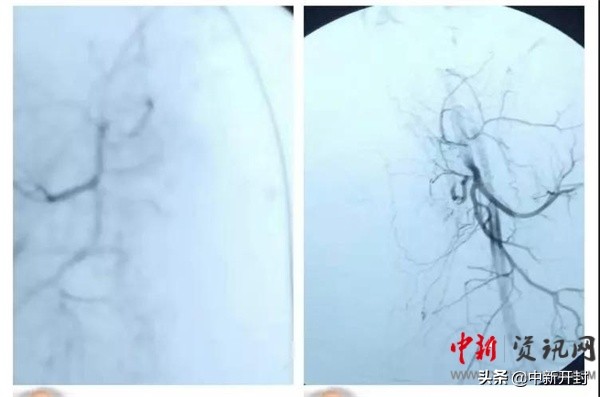

患者病情危重,给予经口气管插管呼吸机供氧,患者出血量大,8.19上午急诊入介入室行子宫动脉栓塞术,术后置管行血液净化治疗,时间就是生命,我们尽我们所能去救助一位孩子的妈妈。